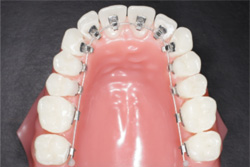

¡Ú¾ÉÎã1¡Û¥Þ¥ë¥Á¥Ö¥é¥±¥Ã¥ÈË¡¤Ç¼£ÎŤò¹Ô¤Ã¤¿À®¿Í¶ºÀµ¤Î¾ÉÎã

- ¼£ÎÅÁ°

- ¼£ÎÅÃæ

- ¼£ÎŸå

- ¥Þ¥ë¥Á¥Ö¥é¥±¥Ã¥ÈË¡¤Ç¼£ÎŤò¹Ô¤Ã¤¿À®¿Í¶ºÀµ¤Î¾ÉÎã

´µ¼ÔÍͤξɾõ

Angle Iµé¡¢±±»õ¤Î³ú¤ß¹ç¤ï¤»¤ËÁ°¸åÊý¸þ¡¢Æâ³°¤ÎÊý¸þ¤Î³ú¤ß¹ç¤ï¤»¤Î¤º¤ì¤Ïǧ¤á¤Þ¤»¤ó¤Ç¤·¤¿¤¬¡¢Á°»õ¤Î¥¹¥Ú¡¼¥¹ÉÔÂ(Í𹺻õ)¤È±¦Â¦¤Î¦ÀÚ»õ¤Î¸òºµÒû¹ç(ËÜÍè¡¢¾å¤Î»õ¤¬³°Â¦¡¢²¼¤Î»õ¤¬Æâ¦¤Ë¤¢¤ë¤â¤Î¤¬¡¢µÕ¤Ë¤Ê¤Ã¤Æ¤¤¤ë¾õÂÖ)¤òǧ¤á¤Þ¤·¤¿¡£

¤Þ¤¿¡¢¾å¤Î¦ÀÚ»õ¤Ïâä¾®»õ¤È¤Ê¤Ã¤Æ¤¤¤Þ¤·¤¿¡£ -

¼£ÎÅË¡

¾å¤Î¦ÀÚ»õ¤¬âä¾®»õ¤Ç¡¢¥µ¥¤¥º¤¬¾®¤µ¤¤¤¿¤á¡¢¾å²¼¤ÎÁ°»õ¤Î¥µ¥¤¥º¥Ð¥é¥ó¥¹¤¬°¤¤¾õÂ֤Ǥ·¤¿¡£

¤½¤Î¤¿¤á¡¢º¸²¼¤ÎÁ°»õ1ËܤòÈ´»õ¤·¤Æ¡¢¥µ¥¤¥º¥Ð¥é¥ó¥¹¤òÀ°¤¨¤ë¤È¤È¤â¤Ë¡¢»õÊÂ¤Ó¤ÎÆÌ±ú¤ò¤Û¤°¤¹¤¿¤á¤Î¥¹¥Ú¡¼¥¹¤È¤·¤ÆÍøÍѤ·¤Þ¤·¤¿¡£

¥Þ¥ë¥Á¥Ö¥é¥±¥Ã¥ÈÁõÃÖ¤òÁõÃ夷¡¢ÇÓÎó¤ò¹Ô¤¤¤Þ¤·¤¿¡£ -

¼£ÎÅ·ë²Ì

¸òºµÒû¹ç¡¢ÁÑÀ¸¤Ï²þÁ±¤·¡¢¤¤ì¤¤¤ËÇÓÎ󤵤ì¤Þ¤·¤¿¡£